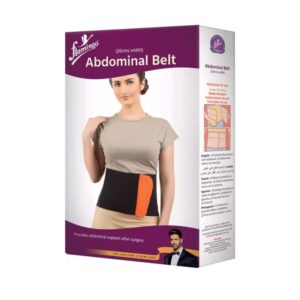

Marque: AURAFIX

AURAFIX Chevillère De Soutien Ligamentaire REF:3400

- Délai de livraison : entre 1 et 3 jours ouvrables

- Produit Original

- Livraison gratuite Stopdesk: Commande +10000DA